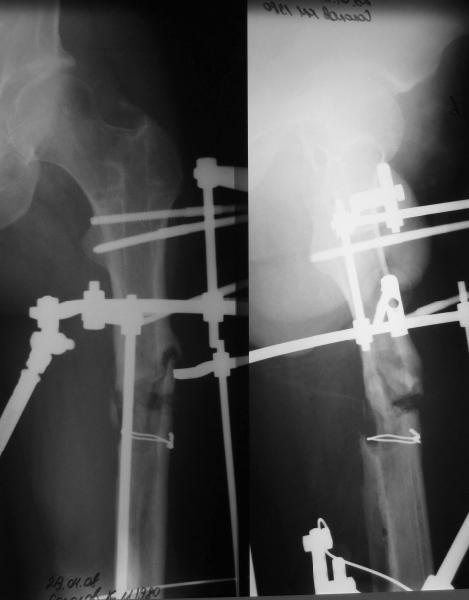

фото несращения бедра

Имя     : фото 6б.jpe

Имя     : фото 6а.jpe